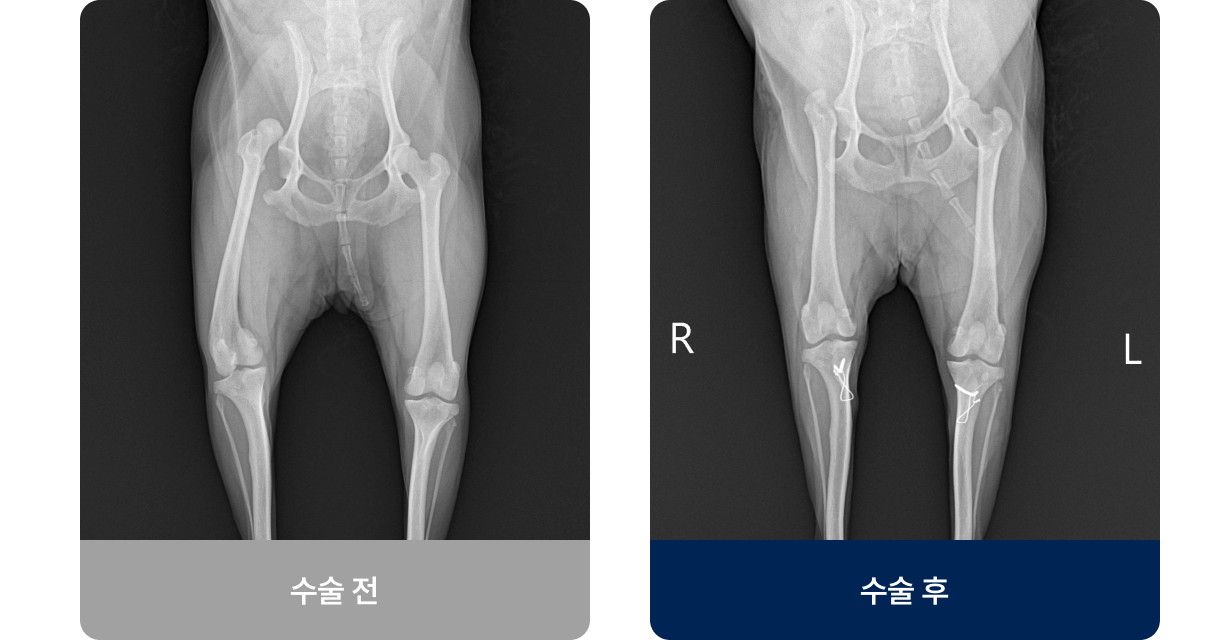

슬개골(무릎뼈)이 대퇴골 고랑에서 안쪽(내측)으로 빠지는 상태로, 소형견에서 자주 발생하는 관절 질환입니다. 주로 선천적인 영향이 대부분이고 후천적인 요인으로는 교통사고나 외부적인 충격으로 발생하며, 일시적으로 다리를 들고 서있다가 다시 내려놓는 증상을 보입니다.